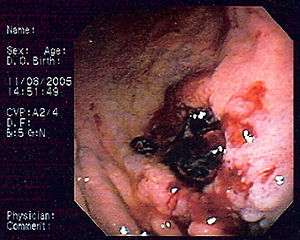

| Endoscopic image of gastric MALT lymphoma taken in body of stomach in patient who presented with upper GI hemorrhage. Appearance is similar to gastric ulcer with adherent clot. | |